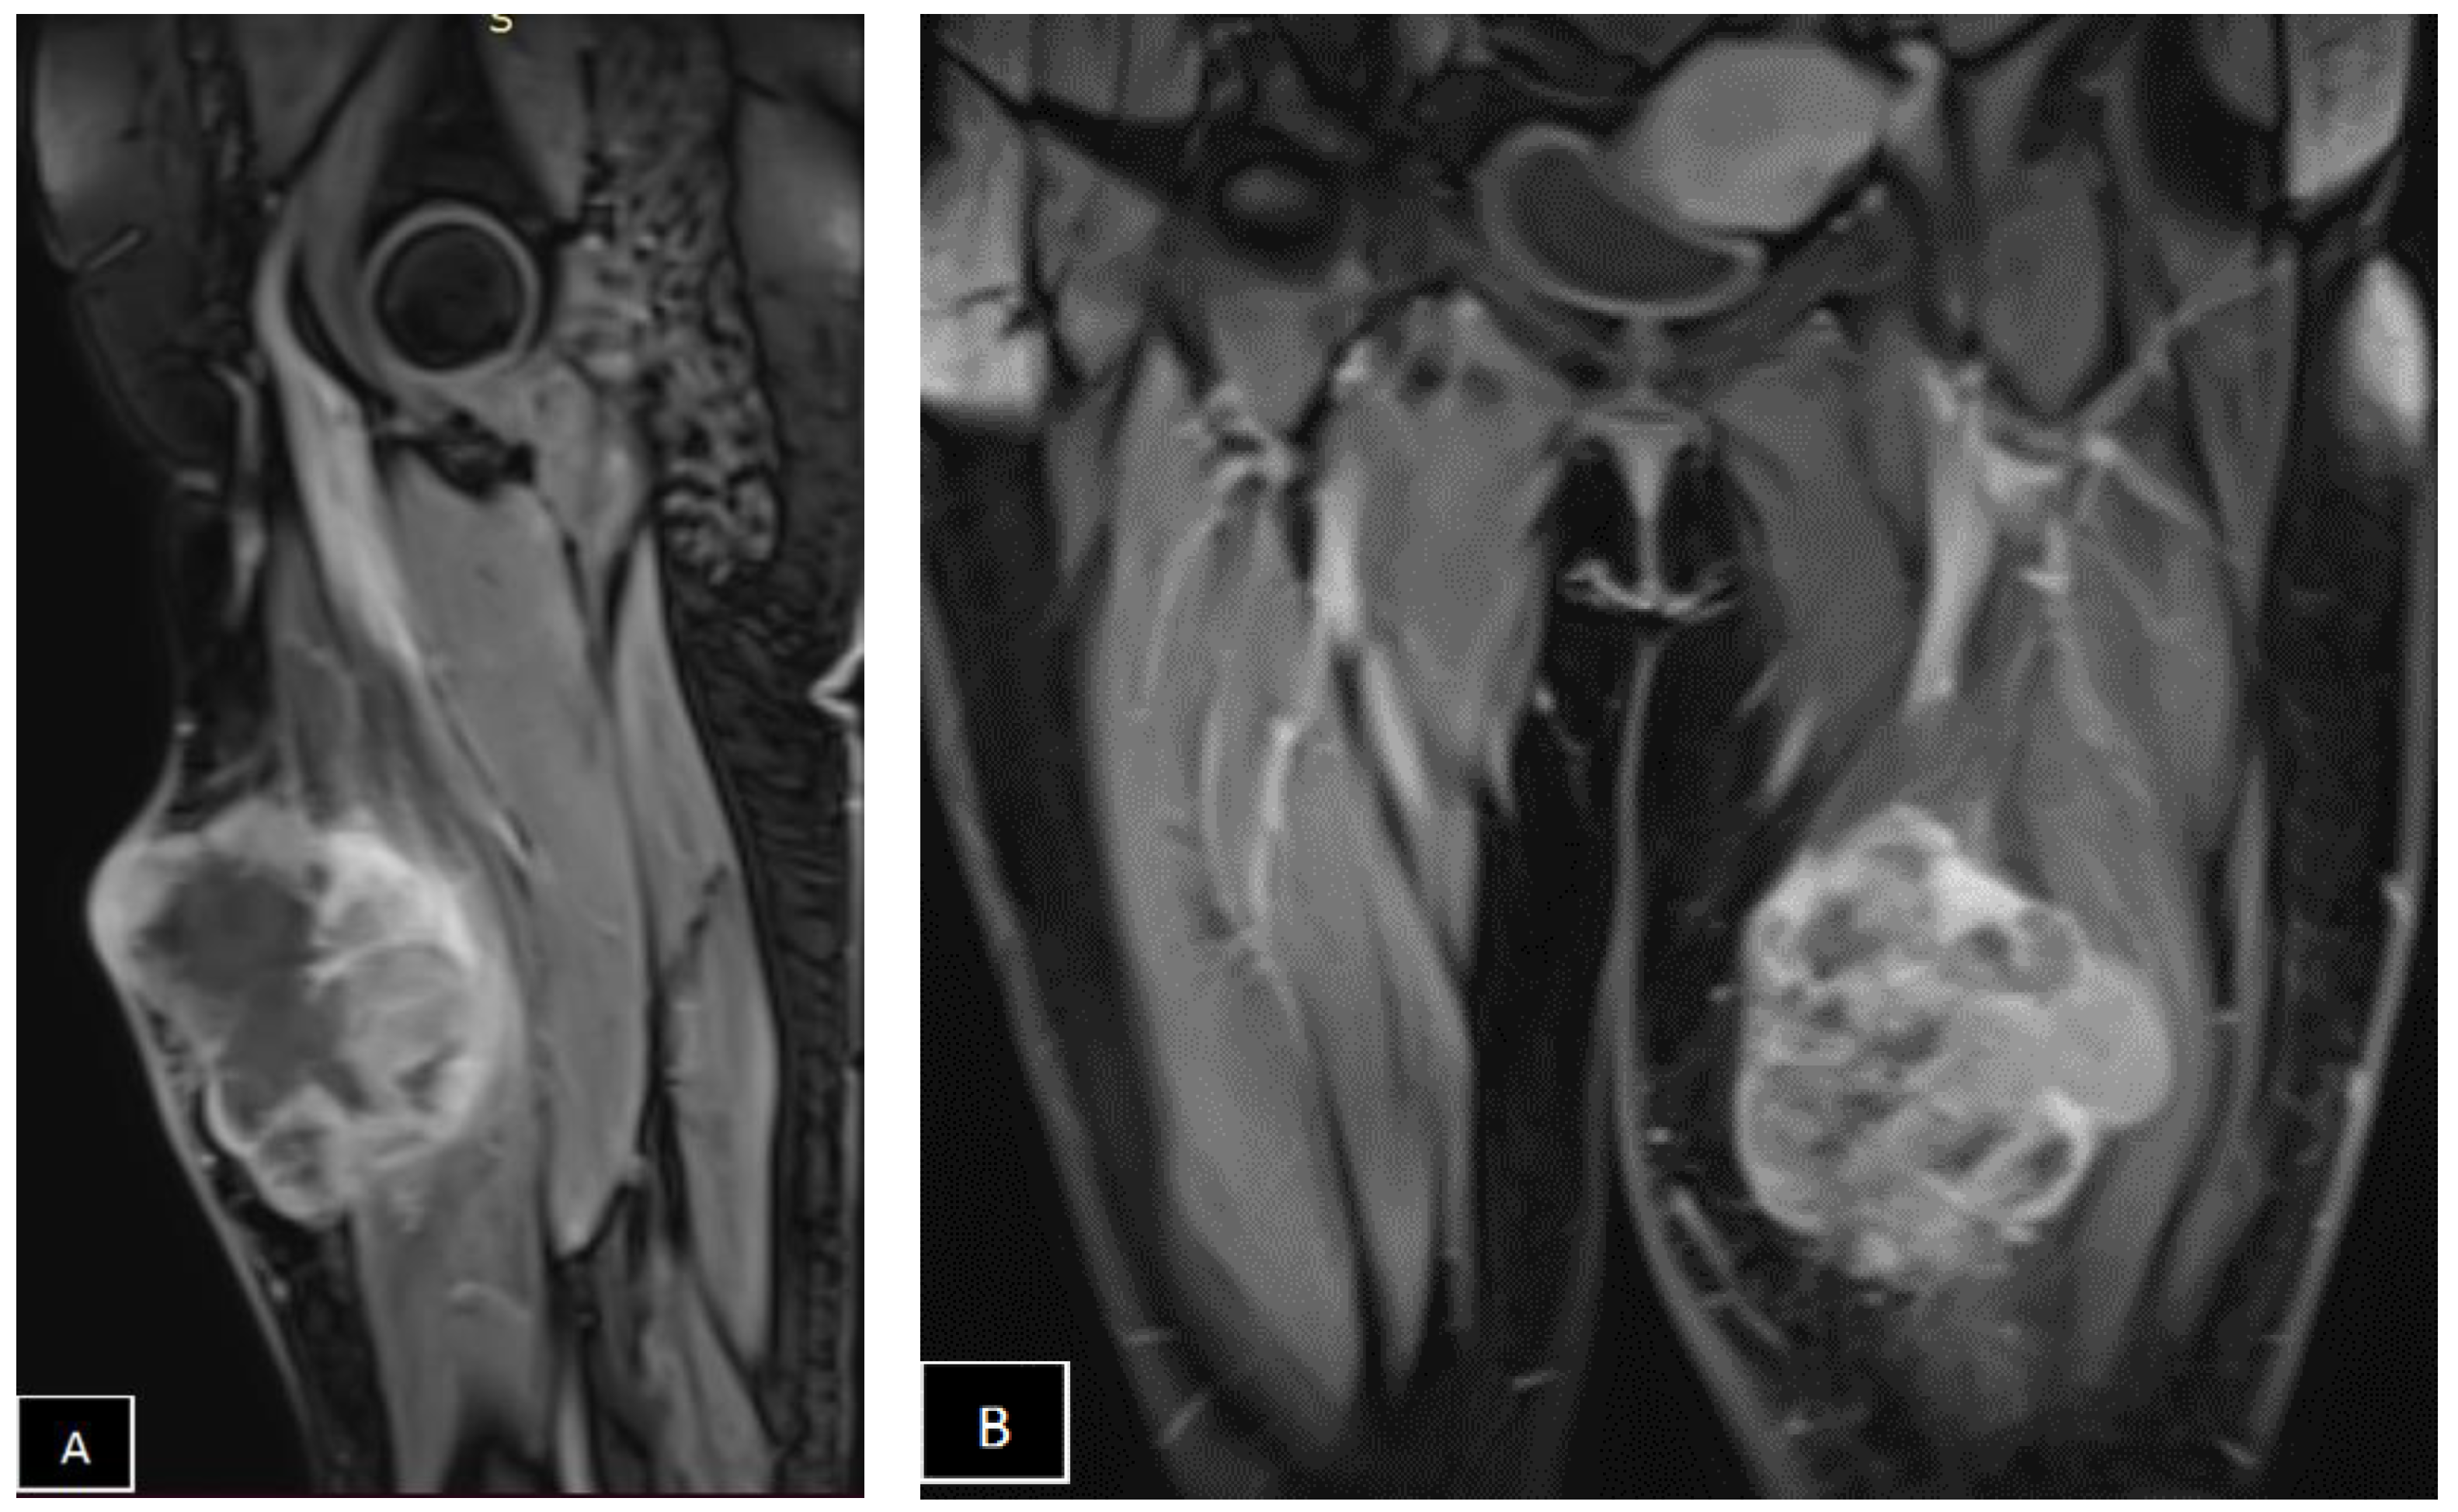

- Spinnato, P.; Clinca, R.; Vara, G.; Cesari, M.; Ponti, F.; Facchini, G.; Longhi, A.; Donati, D.M.; Bianchi, G.; Sambri, A. MRI Features as Prognostic Factors in Myxofibrosarcoma: Proposal of MRI Grading System. Acad. Radiol. 2021, 28, 1524–1529. [Google Scholar] [CrossRef] [PubMed]